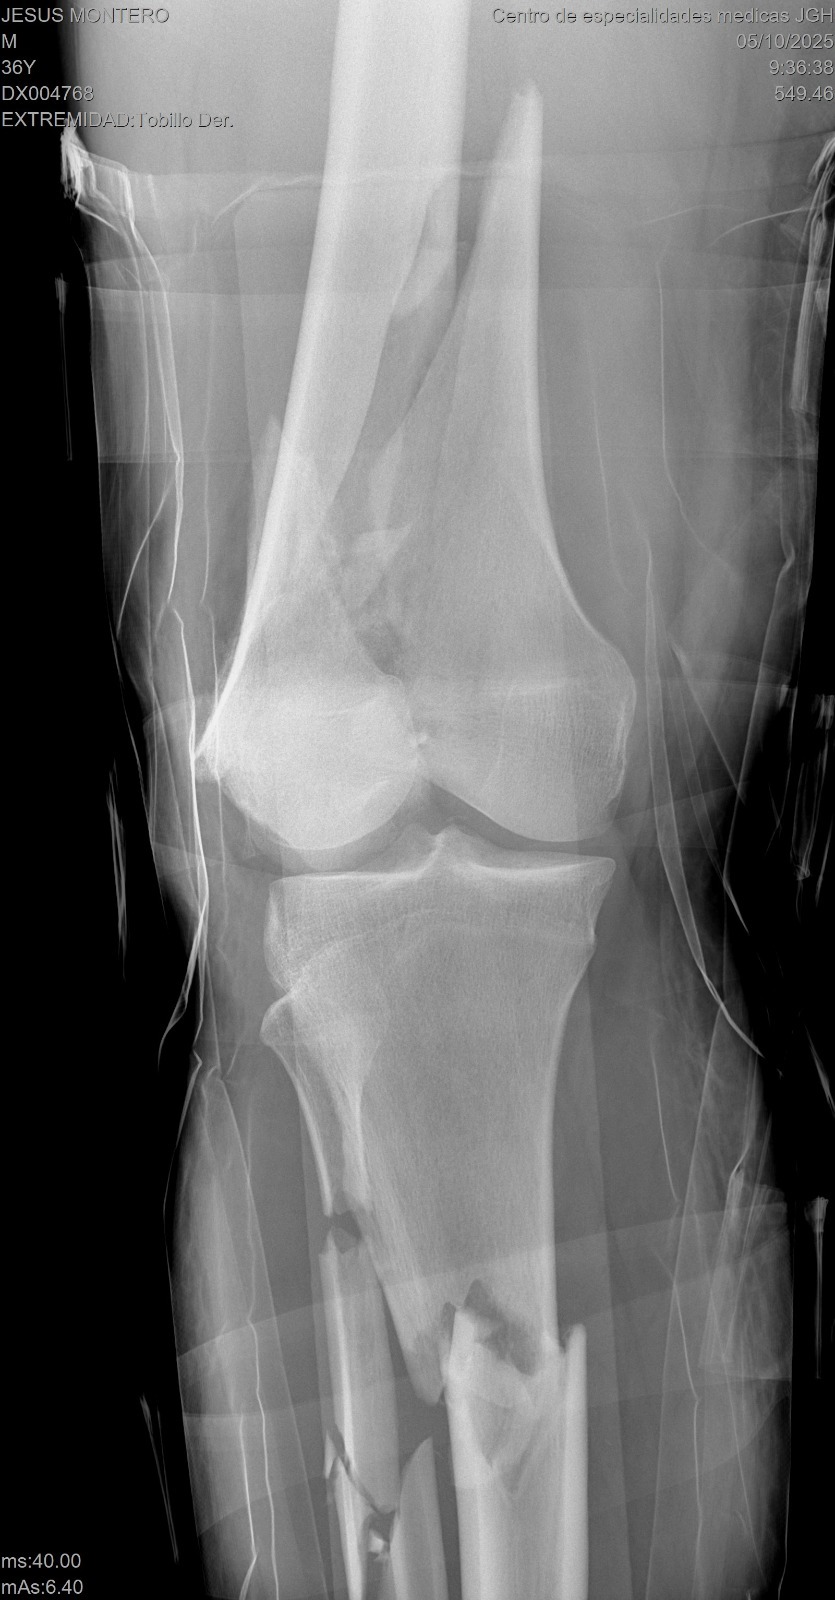

El pasado sábado por la noche, nuestro querido Jesús Montero, ex jugador de Grandes Ligas, sufrió un grave accidente de motocicleta. Actualmente se encuentra en estado delicado, con múltiples fracturas en la pierna, varias costillas rotas, pulmones y organos bastantes comprometidos. Los médicos han debido mantenerlo en un coma inducido para facilitar su oxigenación y estabilizar su condición. Tambien se le estara realizando Dialisis para ayudar al sistema renal.

Jesús continúa en la UCI, bajo pronóstico reservado. Aún sigue en diálisis, ya que sus riñones no han respondido como esperamos. Fue sometido a una cirugía para estabilizar su pierna, y aunque el procedimiento fue exitoso, todavía necesitamos avanzar con una cirugía en la zona del tórax, necesaria para su recuperación.

Last Saturday night, our dear Jesús Montero, former Major League Baseball player, was involved in a serious motorcycle accident. He is currently in critical condition, with multiple fractures in his leg, several broken ribs, and severe lung and organ injuries.

Jesús remains in the ICU, under critical condition. He continues on dialysis, as his kidneys have not yet responded. He recently underwent surgery to stabilize his leg, which was successful, but he still needs to undergo a chest surgery, which is complex but necessary for his recovery.